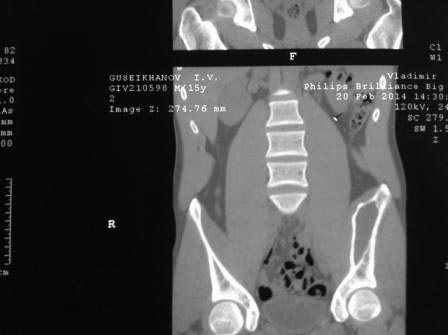

Несмотря на кажущуюся легкость, установить правильный диагноз кисты подвздошной кости бывает сложно. Во-первых, из-за локализации, потому что излюбленным местом костной кисты является проксимальный отдел бедра или плеча, а в тазу киста встречается редко. Еще из-за рентген схожести, кисту ошибочно путают с фиброзной дисплазией, сосудистой кистой или вообще неоплазмой!

Правильный диагноз устанавливается на основании комбинированных исследований: КТ, МРТ, рентген и биопсии. Содержимое кисты обычно чистая серозно-кровянистая жидкость и стенка - реактивная фиброзная мембрана.

Большинство костных кист таза обнаруживается при тазовых исследованиях случайно. А перелом тонких стенок срастается быстро и бессимптомно, но на рентгене остаются дополнительные тени, которые ошибочно принимают за фиброзную дисплазию.

Подвздошная кость в нагрузке не участвует, и при отсутствии клинических симптомов не требуется лечение. Симптоматические можно лечить декомпрессией биопсионной иглой или сверлением.